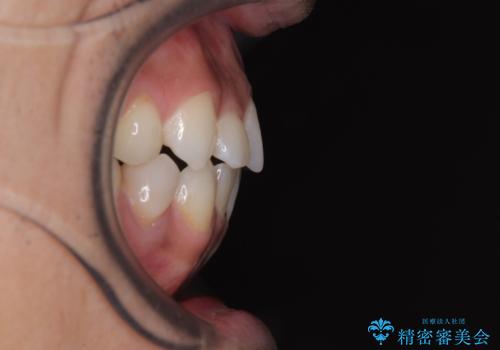

目立たない装置でデコボコを改善 ハーフリンガルによる矯正治療

- 上下顎歯列のデコボコを改善したいとのことで来院された患者様です。

自己管理の大変なインビザラインや、目立つ表側のワイヤー矯正は避けたいとのことで、

上顎だけ裏側装置のハーフリンガルにて矯正しました。

一年と数か月で矯正を終えることができました。